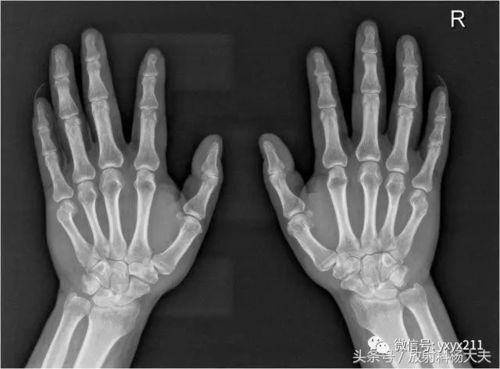

双手骨折图片

骨折x光片